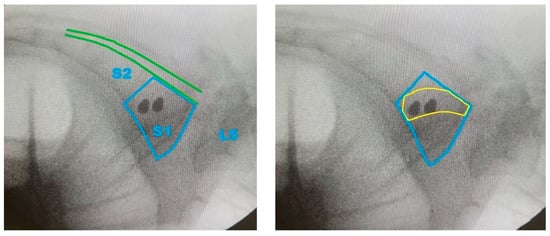

- Generation of Screw Trajectory Target Zone: Using the 2D projection, a patient-specific safe zone for screw placement was identified through a reproducible computational technique developed in this study. The resulting zone is referred to as the Ramadanov–Zabler Safe Zone for reference purposes. Regions with higher bone density were targeted as they suggested a greater likelihood that the screw would remain strictly intraosseous, thereby reducing the risk of cortical breaches or screw misplacement. The target zone served as a guide for the ideal screw trajectory during percutaneous SI screw fixation.

- To support the translational relevance of the proposed technique in a clinical illustration case, we included intraoperative and postoperative imaging from a representative patient with a B-type pelvic injury. The patient underwent standard percutaneous sacroiliac screw fixation. A lateral fluoroscopic image was obtained intraoperatively after guidewire placement, and postoperative CT scans (sagittal and axial) were acquired routinely.